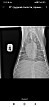

Добрый день!собачка кобель цвергпинчер 14 лет 10 месяцев,стал часто дышать,сделали рентген,помогите понять что с ним!

Добрый день!ренген лёгких у собаки помогите прояснить ситуацию!сделали в связи с частым дыханием

Здравствуйте, у собаки выраженное затемнение по каудальным долям легких. Более всего это похоже на пневмонию.